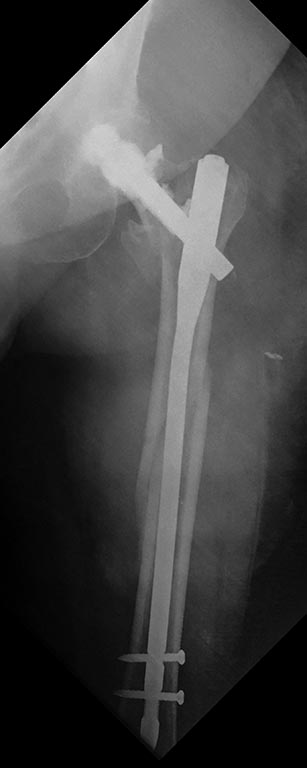

Именно исходя из пункта два был выбран вариант интрамедуллярного

ревизионного остеосинтеза.

Ну, а установить новый длинный гвоздь такого же диаметра - не проблема,

естественно

Новый клинок так же пришлось аугментировать 3 мл специального цемента.